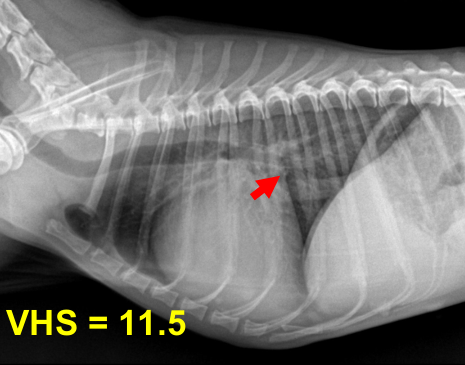

| 2기 (Moderate) |

![]() |

| 기존 소견 동일하게, 1) 심장 커짐 Left auricle 확장, cranial/caudal waist 소실, Globoid heart, Cardiomegaly + Sternal contact 매우 증가 2) 기관 영향 Tracheal elevation, bronchus compression ⇒ Static collapse로 발전 3) 판막, 역류, 심잡음 판막의 thickening (glycose aminoglycan 침착) = Myxomatous degeneration = mitral valve prolapse (MVP, 판막이 뒤로 휨) ⇒ Regurgitation, systolic murmur (심잡음 6단계 중 3단계) 4) 기절 기침 증상이 심하면 syncope (산소 포화도와 혈압이 감소하면서 cardiac output이 감소했기 때문) + interstitial pattern, LA rupture 가능성, 너무 늘어나니 수축이 잘 안 되어 심방부정맥. |